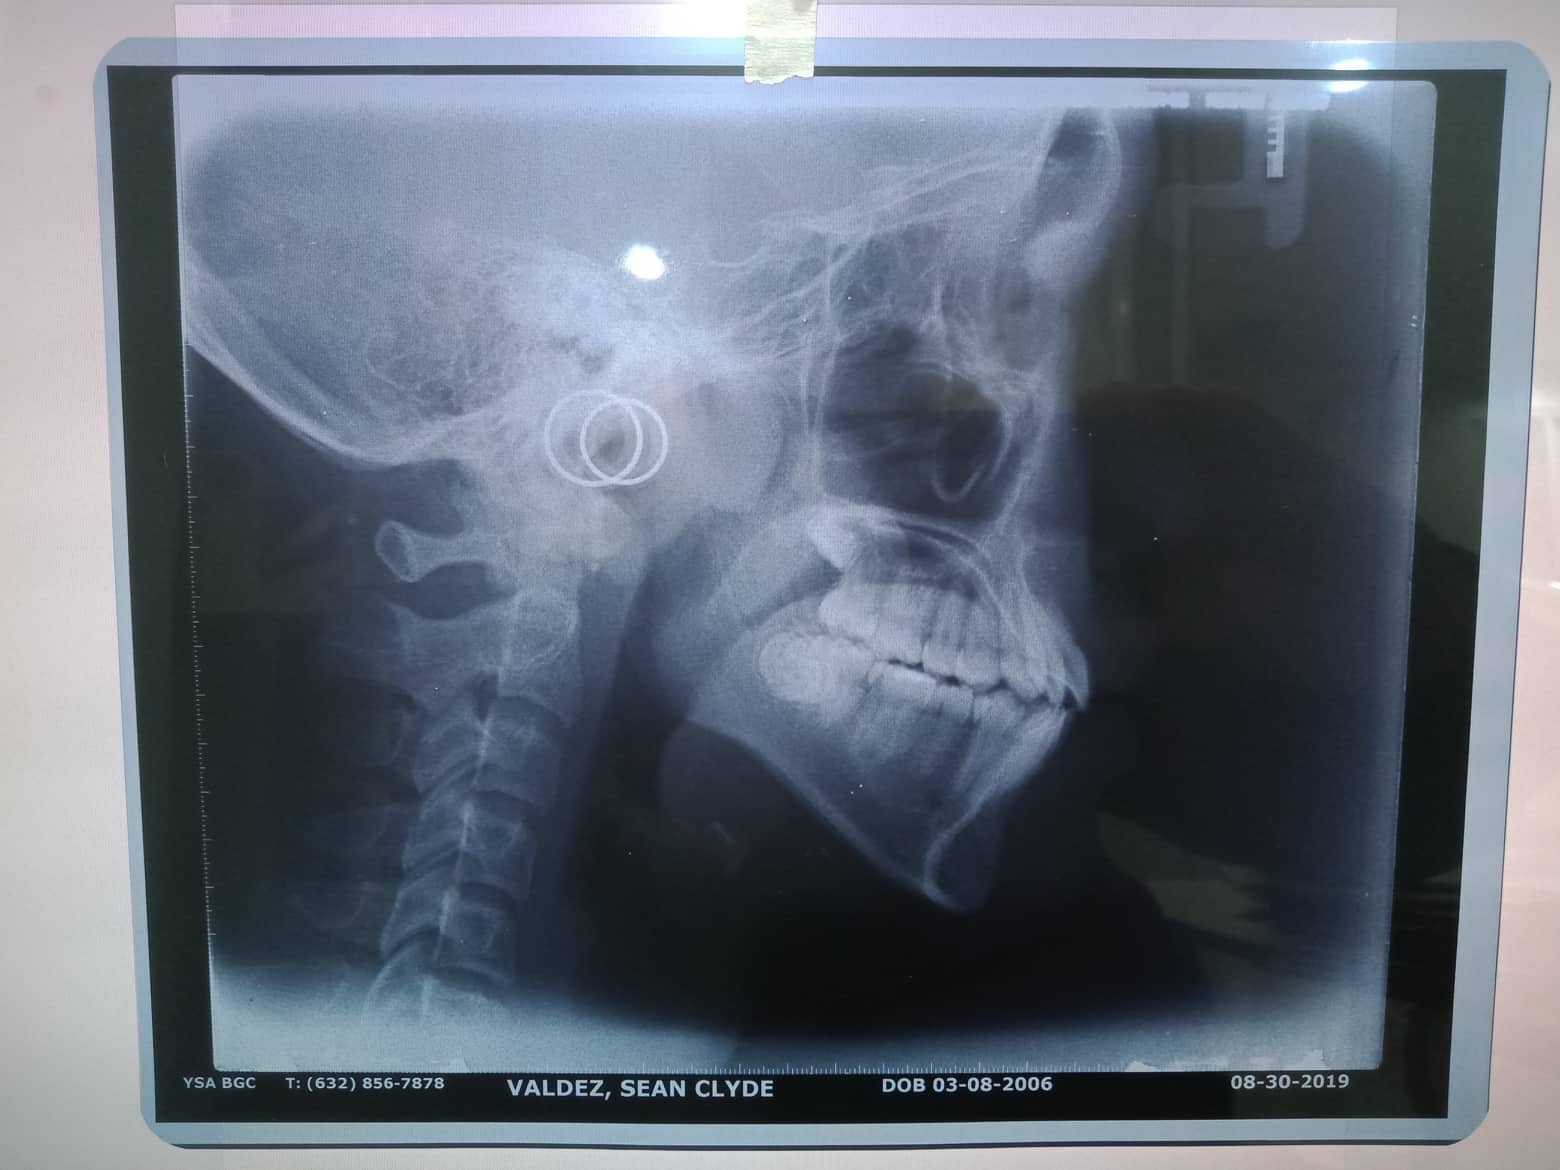

Edit Record Check our patient data records. Add patient information Patient Info Profile picture Last Name First Name Middle Name Birthdate Age Street Barangay City Country Zip Code Contact number Email Procedure 08/28/21- adj 14 nitiL/ 18ssU 11/06/21- 14 niti lower/ 18ss U/ double with 18ss extrude 4 anterior teeth to lock lower ant. canine to canine chipmunk 12/04/21- class 3 penguin./ chipmunk 13-14 to 44/ 23-24 to 34/ same wire 2/19/22- box elastic penguin 13-14-15 to 43-44/ 23-24-25 to 33-34 18 niti lower/ same wire upper next meeting reposition 4 anterior teeth- extrude 04/02/22- adj. 16 ss lower/ 16 ss upper canine to cnine elastic chipmunk ***odontec 5/21/22- 18 ss U/ 16 ss L criss cross elastic 14-45 to 13 -44 / 24-35 to 23-34 monkey class 3 elastic fox 7/23/22- chipmnk 13-14 to 45 same to oTher side reattached #23/ 16 16x16 ss U 8/27/22 - SAME WIRE/ RABBIT BOX 9/24/22 - SAME WIRE 11/18/22-adj/reattached 01/28/23 - same wire 1/27/23-adj 05/07/23 - Adj: L - chain 06/11/23-/same wire/Chain upper and lower/13-43-44 and 23-33-34 elastic chipmunk *FOR ODONTECTOMY 07/09/23-for removal/for odontec 38 adjustment same wire ligature wire upper 08/05/23- #38 Odontectomy/ Gel Foam/ Suture/ Horizontal Class C impaction 08/14/23- removal of suture 09/03/23- Removal of braces/Impression for UL/Retainer w/ Fluoride File 302097495_557515356127090_7489211668915153297_n.jpg File 2 302092195_479311170385623_8495452773336197942_n.jpg File 3 302927078_445401587362306_2447547542471112557_n.jpg File 4 File 5 File 6 File 7 File 8 File 9 File 10 File 11 File 12 File 13 File 14 File 15 File 16 File 17 File 18 File 19 File 20 Retain Record Retain Record Yes No Save Your Changes